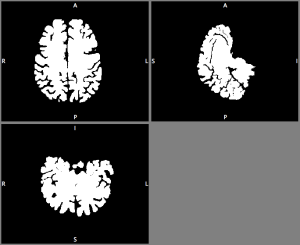

In this blog post, I want to write about pipelines on how to prepare Nifti-brain data and make them printable by a 3D-printer.

Two pipelines are shown. One pipeline describes the 3D-printing the cortical folding structure that is estimated with Freesurfer and subsequently corrected with Meshlab. And another pipeline describes how you can 3D-print any binary nii-volume by using the AFNI-program IsoSurface and correct the output with netfabb.

Pipeline 2: Printing arbitrary 3D-structures in nii with IsoSurface and netfabb

In case you want to 3D-print any other shape of the brain. E.g. entire brain including the cerebellum and brain stem (aseg volume file in FreesSurfer). You can also generate your own surfaces independent of Freesurfer.

This can be done in the AFNI program IsoSurface e.g. with the following command (this command takes less than 60 sec to run).

IsoSurface -isoval 1 -input binary.nii -Tsmooth 0.1 100 -remesh 0.5 -overwrite -autocrop -o Output.stl